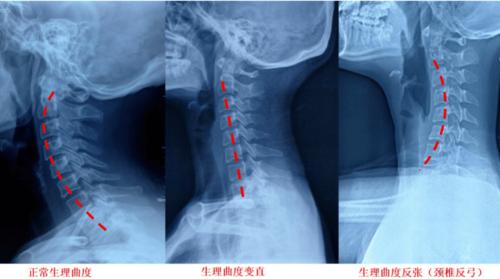

颈椎正常曲度

颈椎正常曲度,颈椎曲度直

颈椎生理曲度变直消失怎么回事

颈椎正常曲度图片

颈椎正常生理曲度图

正常颈椎曲度

正常的颈椎生理曲度

颈椎生理曲度

颈椎曲度变直

颈椎生理曲度变直